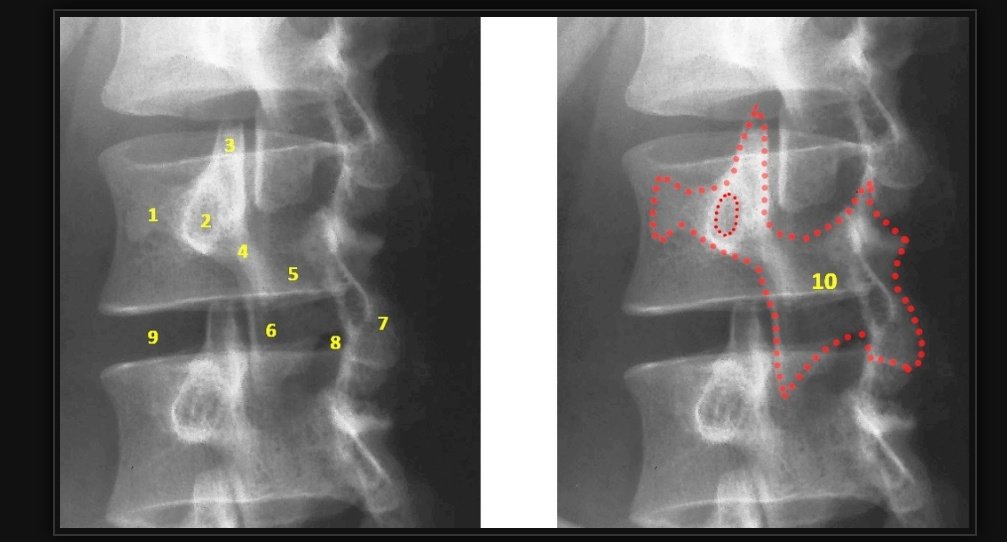

علامة

Scottie dog sign

وتظهر في تصوير العمود الفقري في الوضع المائل

ومن المهم ظهور كافة الأجزاء كدليل على سلامة العضو

أما في حال اختفاء أي جزء كالعين او القدم فيدب على وجود مرض